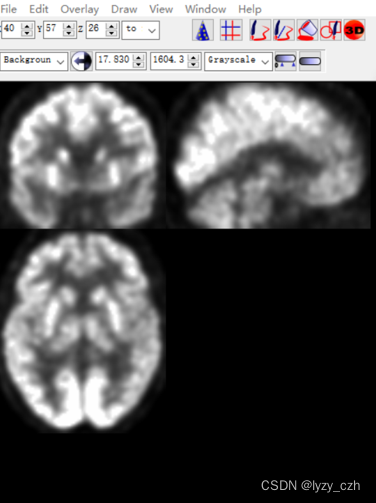

使用MRIcron打开hdr文件如下:MRIcron在我的之前的文章有介绍

点开wmeanxxxx.hdr如下: